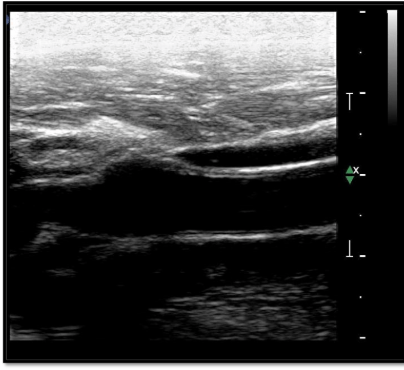

How would you fix this image?

Move near field TGCs to the left and far field TGCs to the right